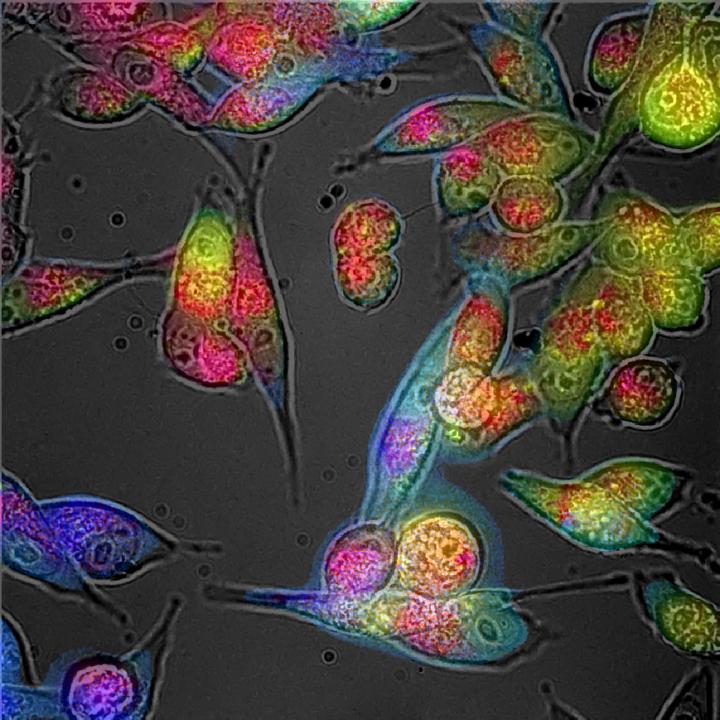

image: An imbalance of unstable molecular species called 'free radicals' will change the colour of cells.

An imbalance of unstable molecular species called 'free radicals' will change the colour of cells - and a new imaging technique could one day allow scientists to detect and decode this colour without needing to take samples from the body, a new study by UNSW Sydney researchers has found.

The microscopic camera works by emitting bursts of low-level LED light at various wavelengths onto cells and tissues. The light is absorbed by fluorescent molecules, which then emit their own light in response.

This fluorescent light allows the researchers to capture detailed maps of cells and tissues via a series of photographs. The microscope then decodes what the colours mean at a molecular level.

"The microscope has a device that precisely captures the colours in the cells," explains Prof Goldys.

"We then use a big data approach to digitally 'unmix' the colour into its molecular components - red, green and blue, for example."